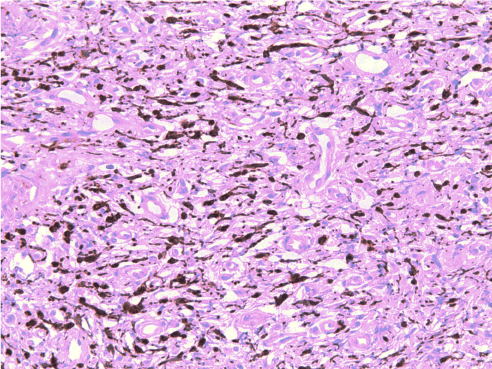

Gingival biopsy was performed and sent for histopathological analysis. The gingival sample revealed a dense spindle-shaped cell proliferation within a fibrillar stroma, associated with capillary and mast cell proliferation, showing no plexiform aspect. Immunohistochemical staining was positive for S-100 protein, EMA (epithelial membrane antigen antibody) and smooth muscle actin (Figure 3). These results were consistent with a benign gingival neurofibroma; the localization indicated that the neurofibroma originated from the lingual nerve.

Figure 3. Immunostaining positive for S100 protein (x200). The tumor cells strongly express the S100 protein (intracytosolic calcium-binding protein), a biological marker of neurological pathologies